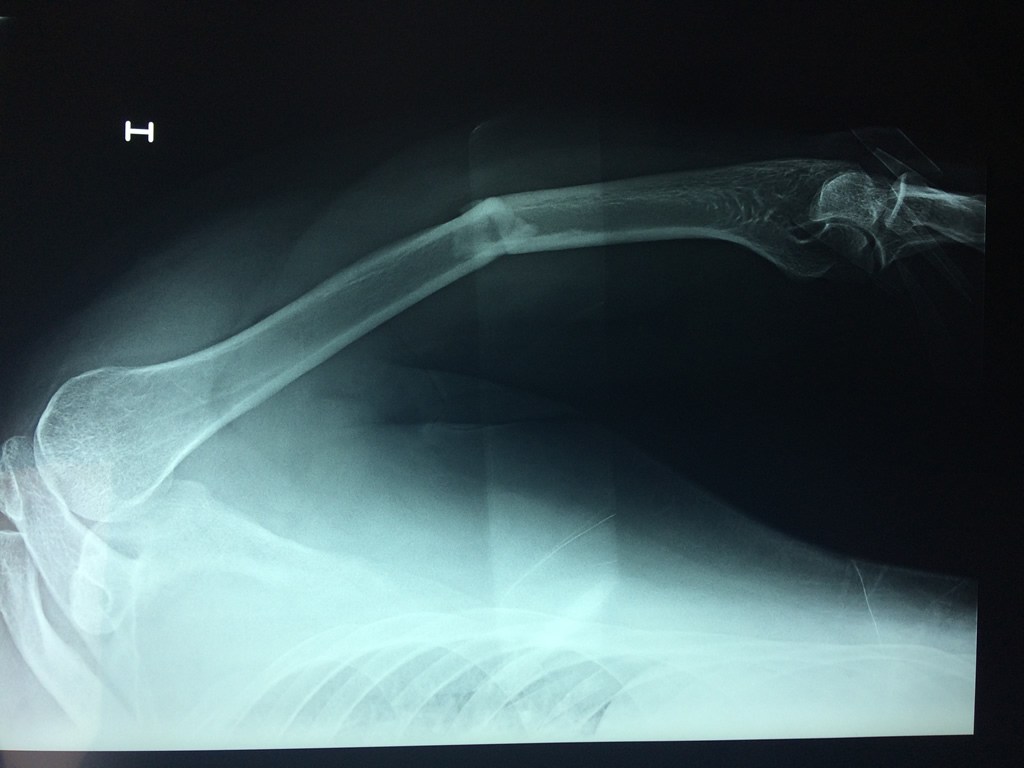

Cirugías de Codo - Húmero

El Húmero (en latín, humerus) es el hueso más largo de las extremidades superiores en el ser humano. Forma parte del esqueleto apendicular superior y está ubicado en la región del brazo. ... El extremo proximal del húmero tiene la cabeza, cuellos quirúrgico y anatómico y tubérculos mayor y menor.